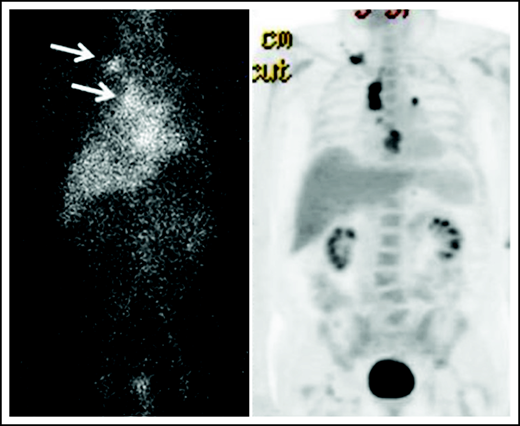

Biodistribution of 111In-basiliximab/DOTA at 144 hours in UPN-1 (left) and 18F-FDG-PET (right).

Twenty-five patients received an imaging dose of cold basiliximab and 111In-basiliximab-DOTA. Two patients had altered biodistribution and did not proceed to receive a therapeutic dose. One of those patients had increased blood pool activity in their 144-hour 111In scan, and 1 patient had increased left posterior-lung activity compared with the heart. Organ dosimetry was evaluated for 3 patients treated at each dose level and the 2 patients who had altered imaging biodistribution. Cumulative absorbed doses to key organs from the 3 patients analyzed at each therapeutic dose level are shown in supplemental Table 6. The patients with altered biodistribution would not have had significantly higher organ doses of 90Y compared with the average dose across all patients evaluated. For the 2 patients with altered biodistribution, the heart wall and the spleen received the highest doses: 11.6 and 9.6 mGy/MBq (heart wall) and 8.6 and 9.9 mGy/MBq (spleen), which were not appreciably different than the average for all patients of 10.3 ± 1.7 mGy/MBq in the heart wall and 13.1 ± 4.3 mGy/MBq in the spleen. The lungs of the 2 patients with altered biodistribution received 6.1 and 5.2 mGy/MBq while the average dose for all patients on the 0.6 mCi/kg dose was 6.3 ± 1.4 mGy/MBq, and their red marrow dose was 1.0 and 0.9 mGy/MBq, which was similar to the average dose for patients on all dose levels (0.9 ± 0.1 mGy/MBq). We examined plasma half-life of basiliximab in the two-compartment model for all dose levels: the mean ± standard deviation T1/2 for the α and β phases was 13.2 ± 13.9 hours and 168.7 ± 118.3 hours, respectively. PK curves of the 111In-basiliximab clearance in the blood and serum and accumulation of 111In-basiliximab in the urine are shown in Figure 2. No delayed blood or serum clearance or increased urine accumulation was observed.